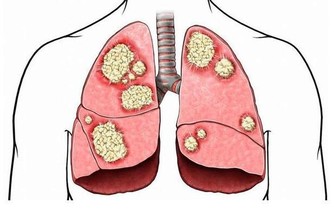

談到心肌梗塞,大家總是把這個好發於寒冷季節的疾病,跟年長的男性聯想在一起。

但是您­可能不知道,除了年輕族群的發生率有上升的趨勢,

其實女性罹患心肌梗塞的死亡率比男性­更高,

甚至遠比我們常說的乳癌、子宮頸癌等女性常見癌症死亡率還要高得多。

根據研究,女性罹患心肌梗塞的症狀其實和男性並不相同,以致於很容易被忽略而失去了搶­救的先機。